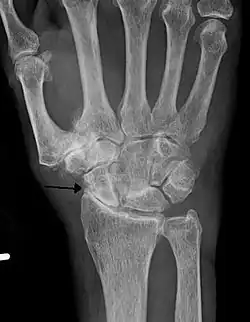

Diagnosis is made with reasonable certainty based on history and clinical examination.[52][53] X-rays may confirm the diagnosis. The typical changes seen on X-ray include: joint space narrowing, subchondral sclerosis (increased bone formation around the joint), subchondral cyst formation, and osteophytes.[54] Plain films may not correlate with the findings on physical examination or with the degree of pain.[55]

Primary osteoarthritis of the left knee. Note the osteophytes, narrowing of the joint space (arrow), and increased subchondral bone density (arrow). -